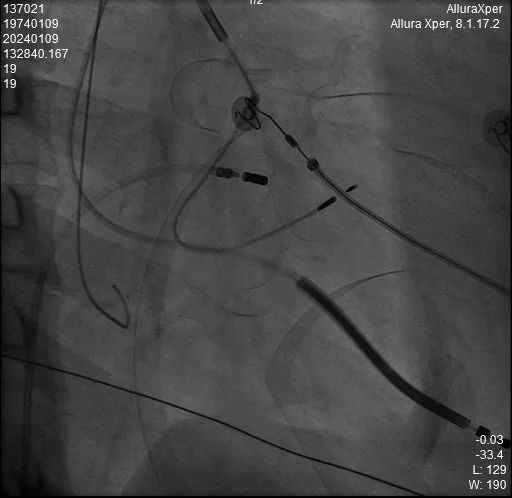

术中HIS电极影像

LBB影像位置

术中影像 HIS-HISD-消融靶点